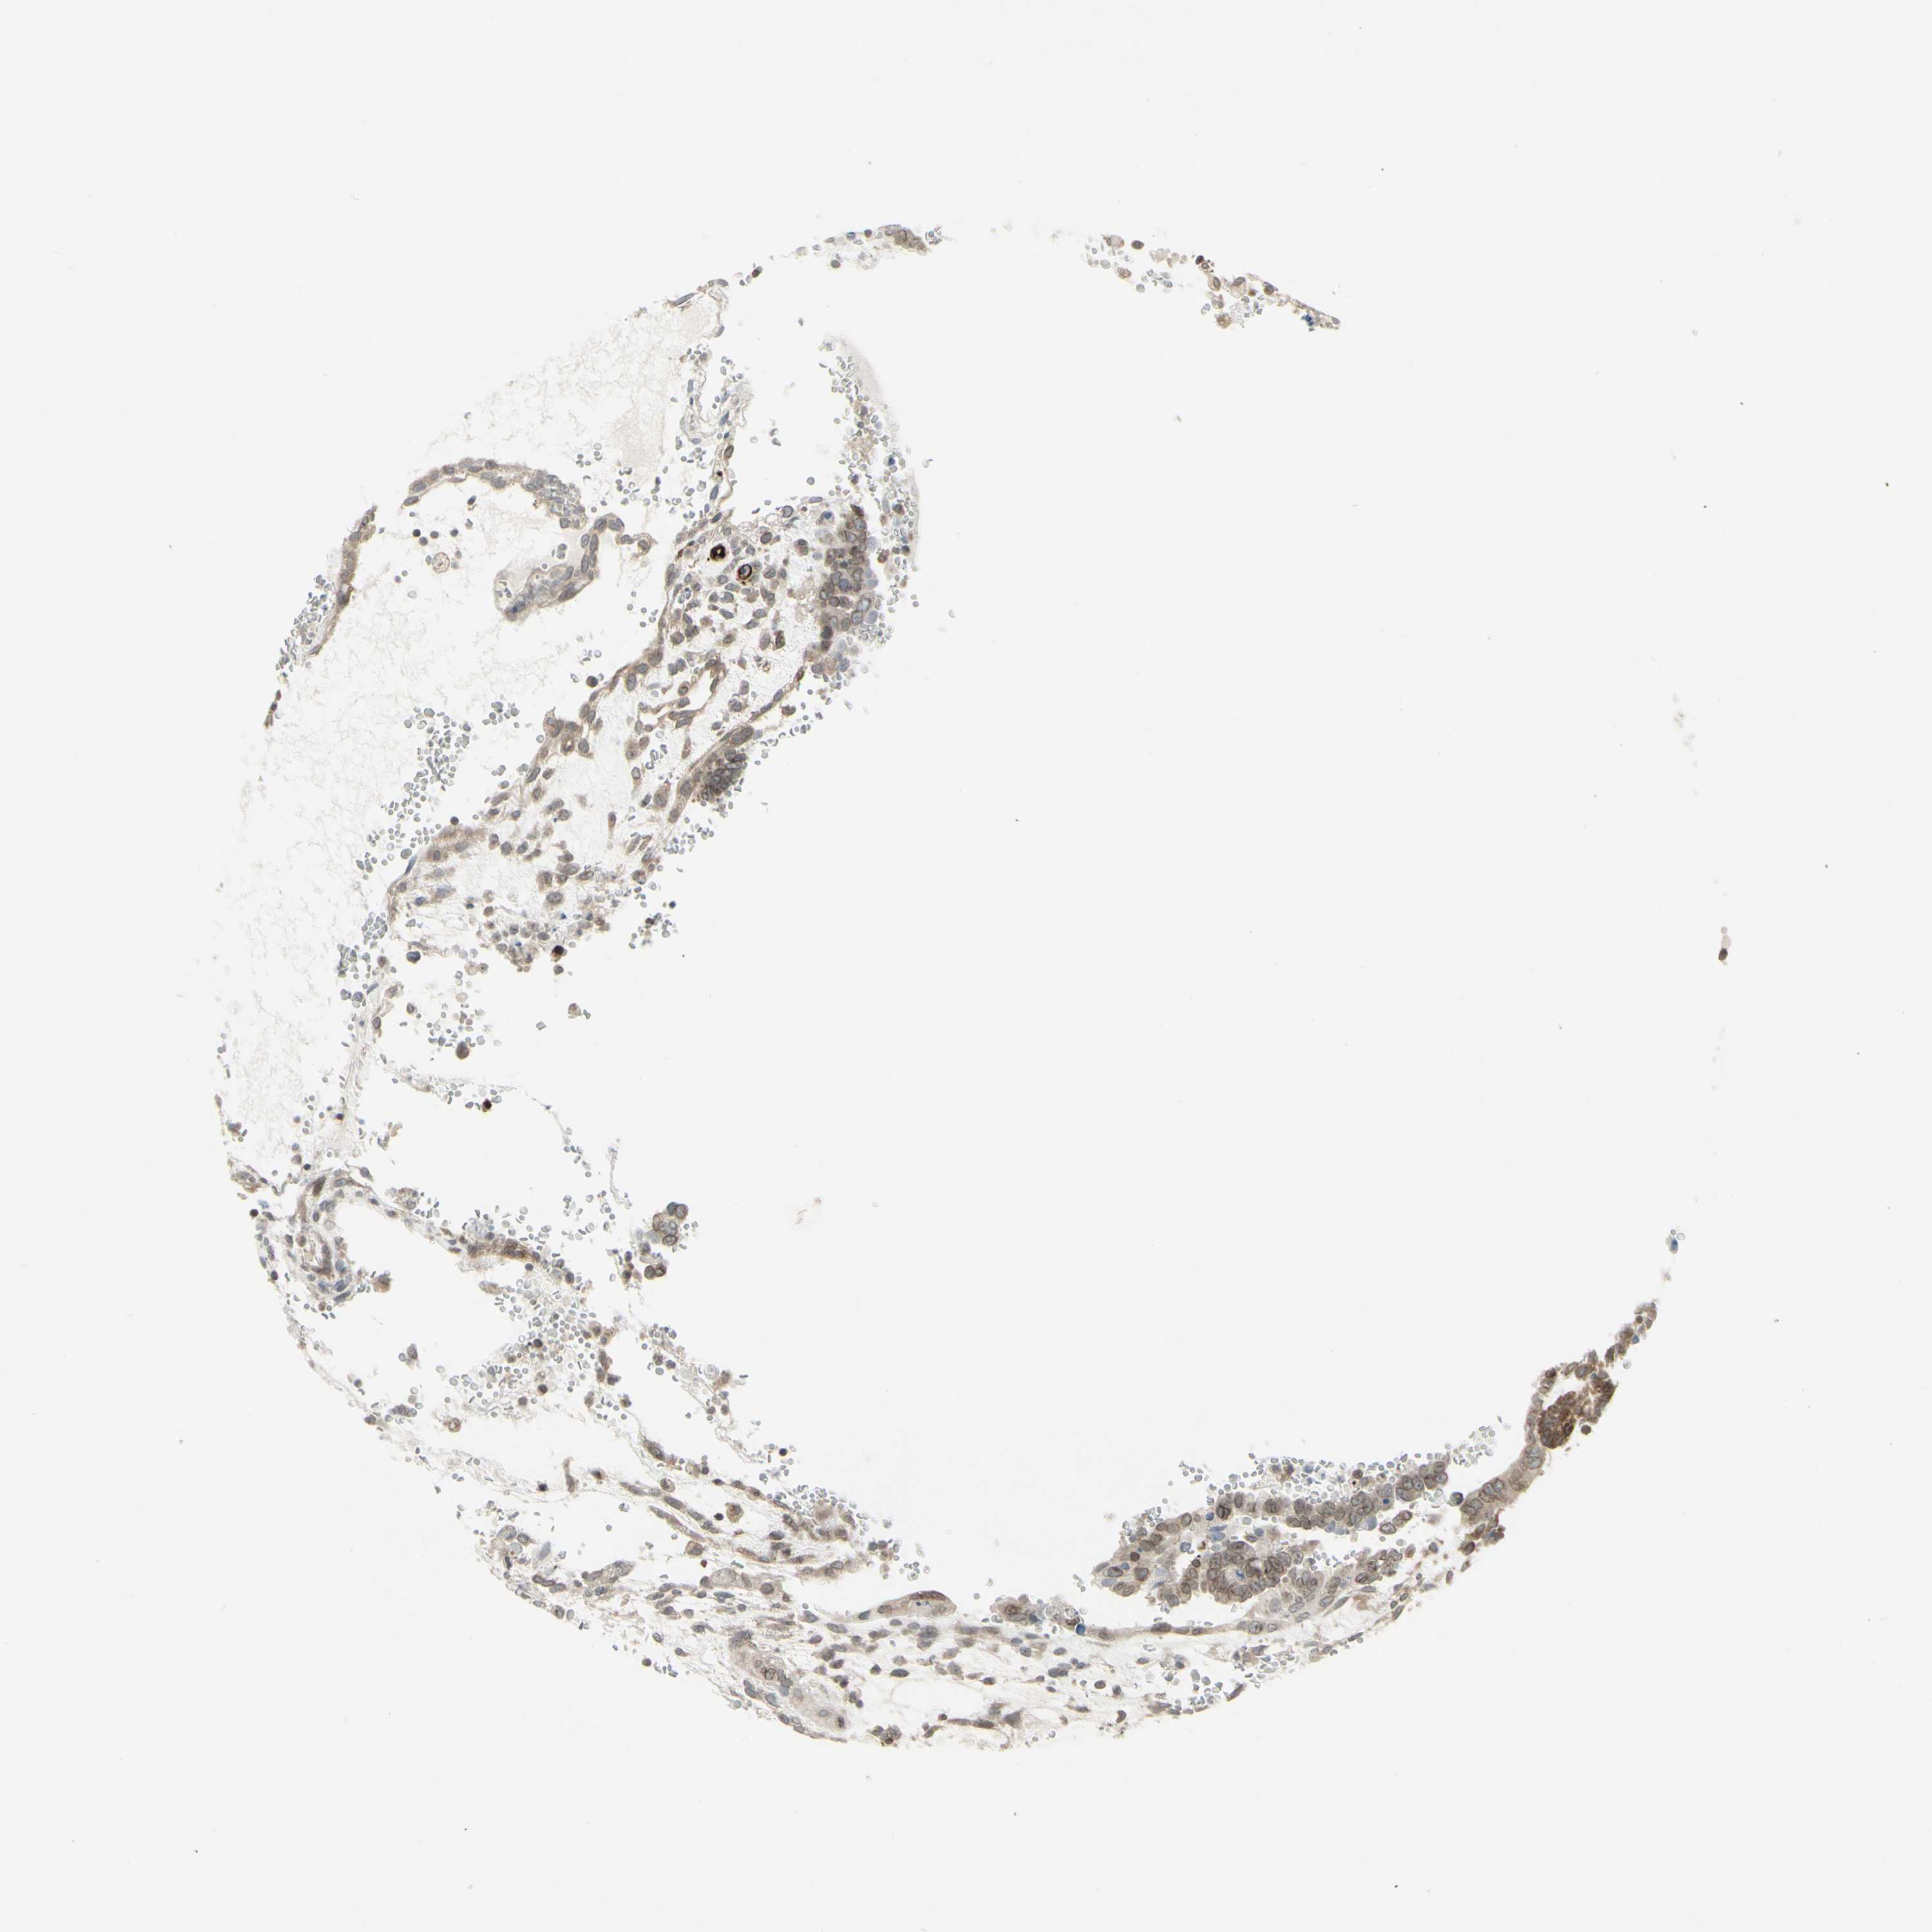

TESTIS CANCER - Protein expressioni

A mouse-over function shows sample information and annotation data. Click on an image to view it in a full screen mode. Samples can be filtered based on level of antibody staining by selecting one or several of the following categories: high, medium, low and not detected. The assay and annotation is described here.

Note that samples used for immunohistochemistry by the Human Protein Atlas do not correspond to samples in the TCGA dataset.

Antibody stainingi

Antibody staining in the annotated cell types in the current human tissue is reported as not detected, low, medium, or high, based on conventional immunohistochemistry profiling in selected tissues. This score is based on the combination of the staining intensity and fraction of stained cells.

Each image is clickable and will lead to virtual microscopy that enables deeper exploration of all samples and also displays staining intensity scores, fraction scores and subcellular localization as well as patient and tissue information for each sample.

Antibody HPA010570

Carcinoma, Embryonal, NOS

Seminoma, NOS